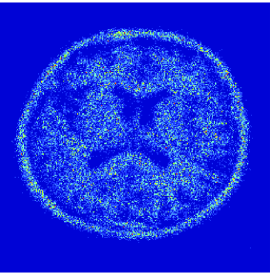

At this point, it may be interesting to compare the proposed extension with the approach developed in [24]. The use of the Anscombe transform [2], in [24] is actually tantamount to approximating the anti log-likelihood of the Poisson distribution by

The proposed quadratic extension is illustrated in Fig. 4 where a graphical comparison with the Anscombe approximation is performed.

Here, is a uniform blur with . A () medical image shown in Fig. 5(a) is degraded by and corrupted by a Poisson noise following the model described in the previous section for various intensity levels. The degraded image is displayed in Fig. 5(b) when .

To evaluate the performance of our algorithm we use the Signal to Noise Ratio defined in Section 5.3.2. Tab. 2 shows the values of the obtained for different values of and . As predicted by Proposition 5.4(v), beyond some value of , which is dependent of , the optimal value is found. We also compare our results with those provided by two different approaches. The first one is the regularized Expectation Maximization (EM) approach (also sometimes called SMART) [10, 31] where the Poisson anti-likelihood penalized by a term proportional to the Kullback-Leibler divergence between the desired solution and a reference image is minimized. Its weighting factor has been adjusted manually so as to maximize the and, the reference image is a constant image whose pixel values has been set to the mean value of the degraded image. The other approach is the method based on the Anscombe transform proposed in [24] and discussed in Remark 5.6. For fair comparisons, the method here employs the same orthonormal wavelet representation, the same functions as ours and the same constraint set . It can be observed that the approach we propose gives good results. However, for high intensity levels (), the method based on the Anscombe transform performs equally well in terms of SNR. The restored images are shown in Fig. 5, when and after 3000 iterations. In spite of an important degradation of the original image, it can be seen that our approach is able to recover the main features in the image. It can also be noticed that the image restored by the two methods exhibit different visual characteristics.

![]() |

| (b) | (c) |

| (d) | (e) |